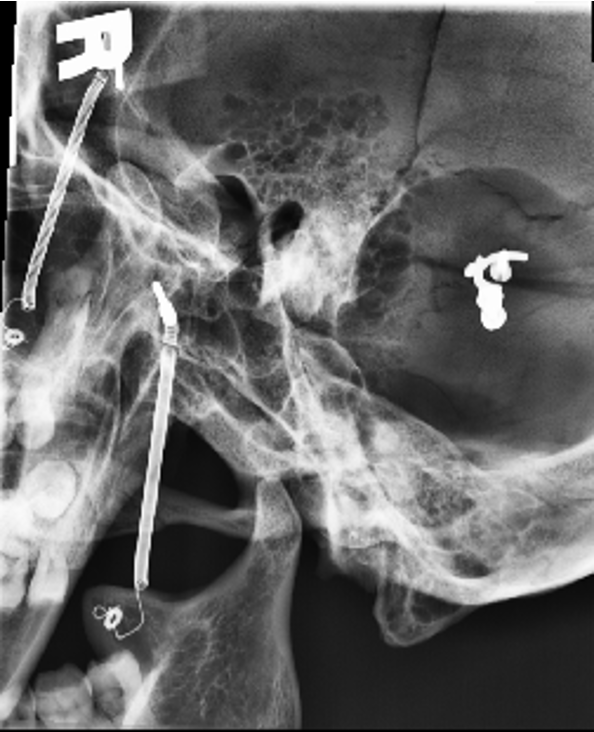

Axiolateral of TMJs - Modified Schuller Method (closed mouth)

Axiolateral of TMJs - Modified Schuller Method (open mouth)

Axiolateral oblique of TMJs - Modified Law Method

Axiolateral of temporomandibular joint - Modified Schuller method (mouth closed)

Axiolateral of temporomandibular joint - Modified Schuller method (mouth opened)

Axiolateral oblique of temporomandibular joint - Modified Law method (open and closed)